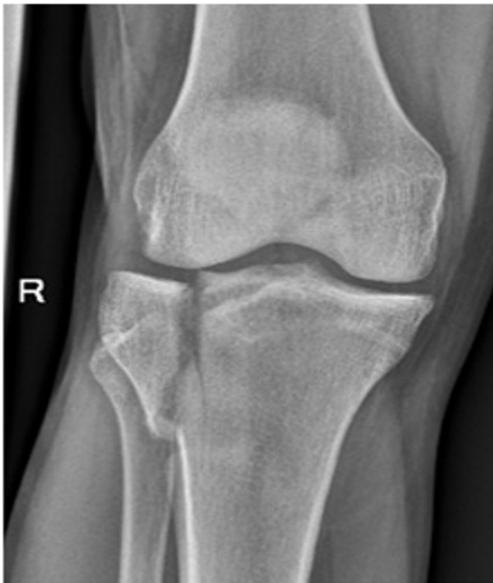

Reading an X-Ray of Osteoarthritic Knee Joint

Five Key Features

- Narrowing of the joint line

- Formation of osteophyte

- Subchondral sclerosis

- Subchondral cyst

- Joint deformity

X-ray AP Lateral Osteophyte formation - joint space narrowing - Subchondral cyst adn sclerosis - joint Varus deformity